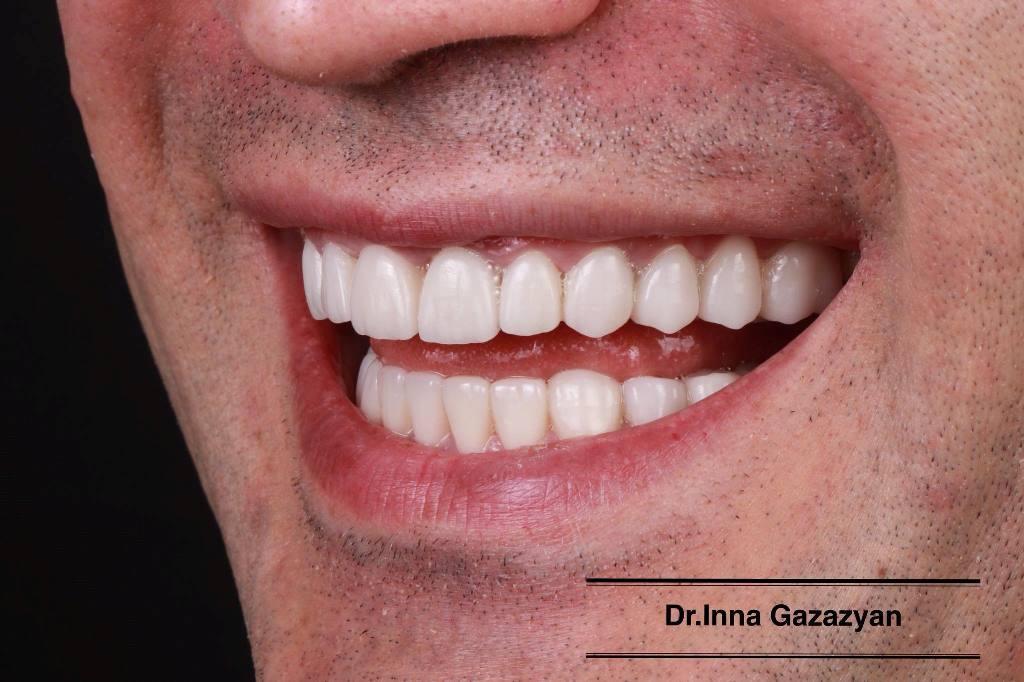

Улыбка звезды: крупный план фотографий передних зубов

Раздел: Фотодневник открытий